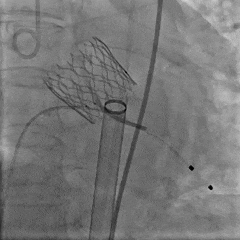

27瓣膜0位释放至全展开

全展开造影,瓣膜位置可,形态稳定

脱钩后造影,瓣膜0位,无反流

术后CT检查

术后CT可见瓣膜展开良好,CA对齐

长轴可见瓣膜位置理想